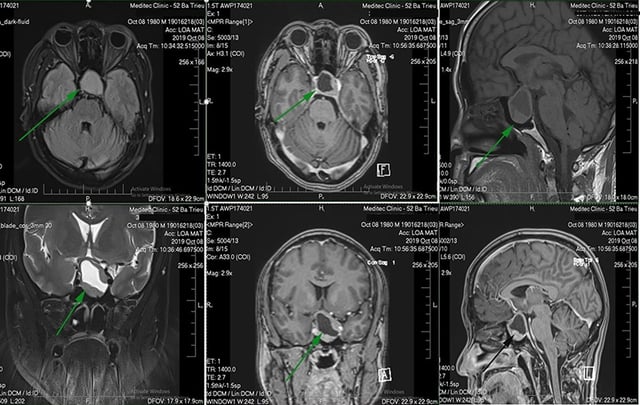

Im Gespräch mit dem Arzt in der Medlatec Tay Ho General Clinic erzählte der Patient, dass er im Jahr 2023 wegen eines Kraniopharyngeoms operiert worden sei. Der Arzt ordnete an, dass der Patient einige notwendige paraklinische Techniken anwenden sollte, um die Diagnose zu stellen.

Die Untersuchungsergebnisse zeigten, dass der Patient nach einer Kraniopharyngeom-Operation an einer postoperativen Hypophyseninsuffizienz litt, einer seltenen endokrinen Erkrankung. Insbesondere die Natriumwerte im Blut zeigten einen Anstieg des osmotischen Blutdrucks und einen Rückgang des osmotischen Urindrucks. Die Ärzte diagnostizierten eine postoperative Hypophyseninsuffizienz nach einer Kraniopharyngeom-Operation und verordneten ihm eine Behandlung sowie die Anweisung, seine Lebensgewohnheiten und Ernährung umzustellen.